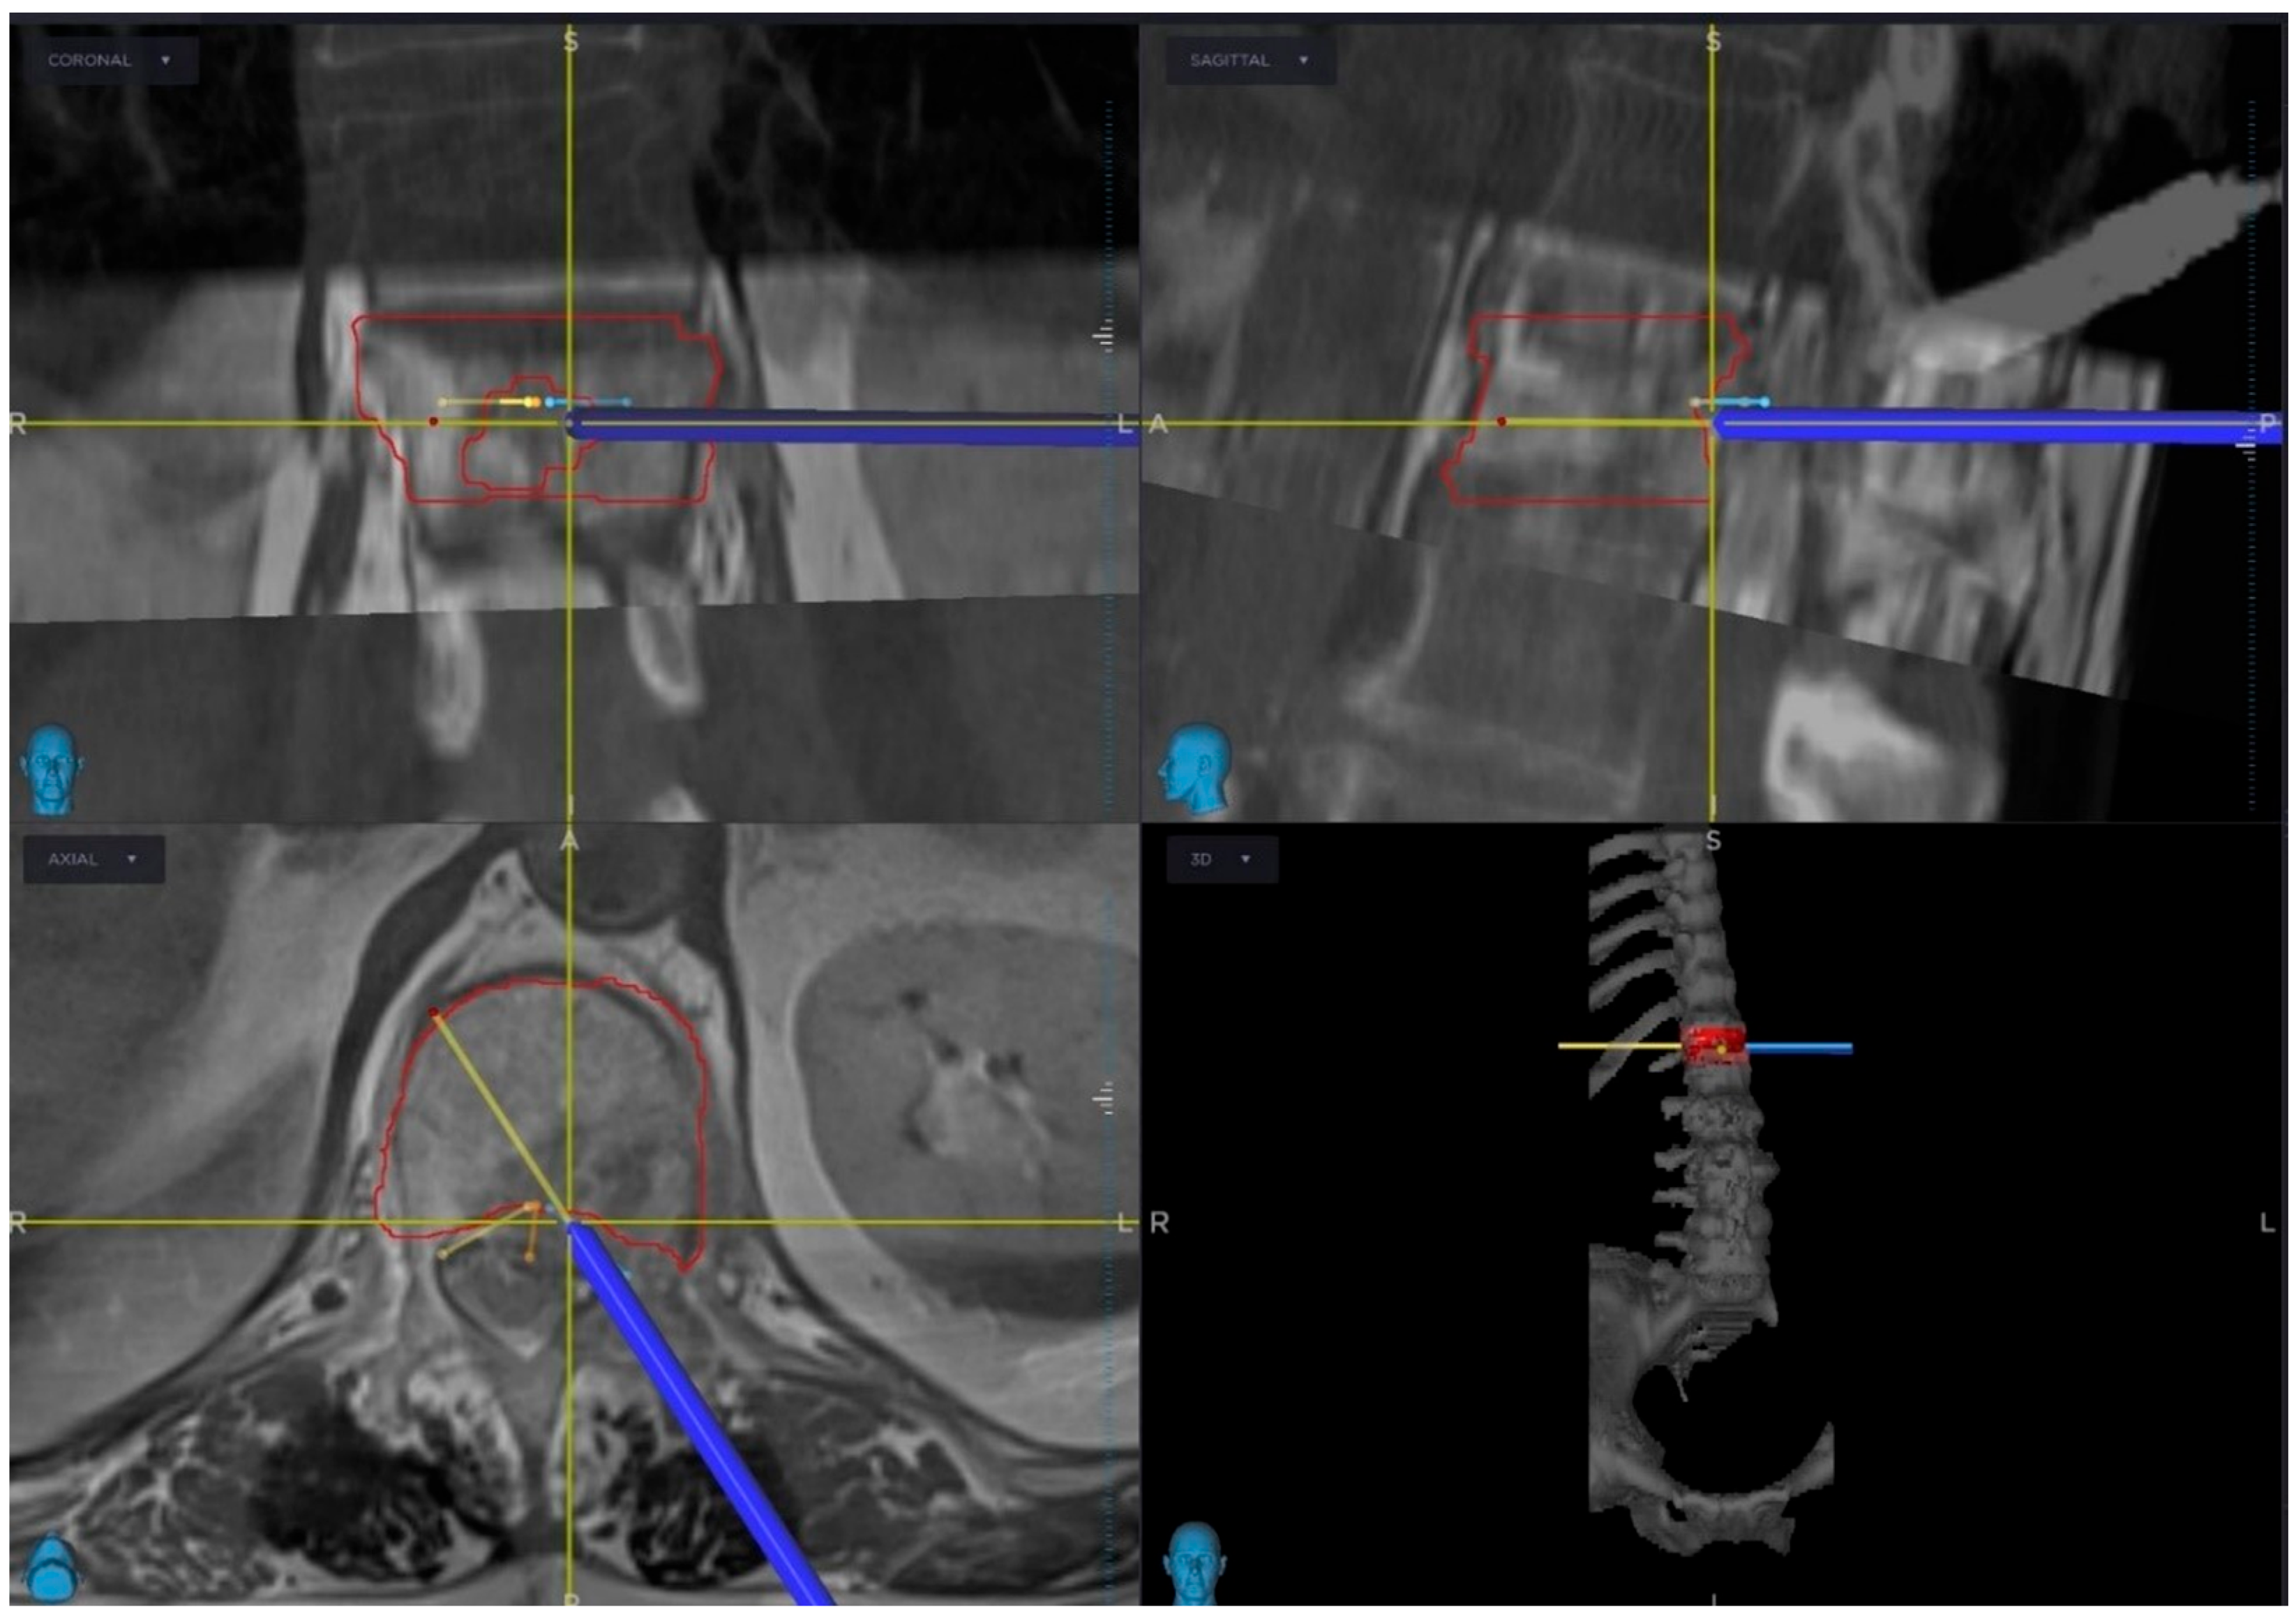

2.2. Pre-Operative Planning and Treatment Strategy

2.3. Radiotherapy Planning and Delivery